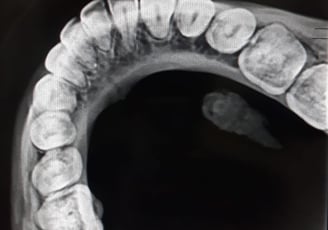

Radiografii occlusale

Radiografiile occlusale sunt utile pentru a evalua relația dintre dinți în timpul mușcării și pentru a depista probleme legate de alinierea dinților